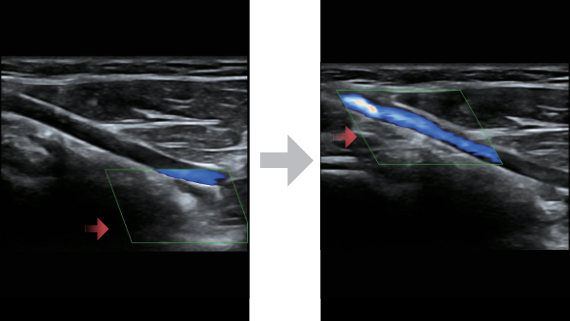

X-Insight ├© una soluzione completa studiata per offrire la migliore qualit├Ā diagnostica.

La nuova soluzione di Mindray ├© la traduzione pratica delle esigenze quotidiane dei clienti in soluzioni cliniche, il tutto con tecnologie ad ultrasuoni all'avanguardia ed in continua evoluzione.

Progettato per rispondere al meglio alle esigenze del cliente, DC-60 Exp con X-Insight ├© studiato per offrire un'efficienza elevata nel campo dell'imaging di precisione, grazie a una chiarezza immediata (eXpress Clarity), allŌĆÖeccezionale intelligenza (eXceptional Intelligence), oltre a vantare una lunghissima esperienza (eXceeding Experience).